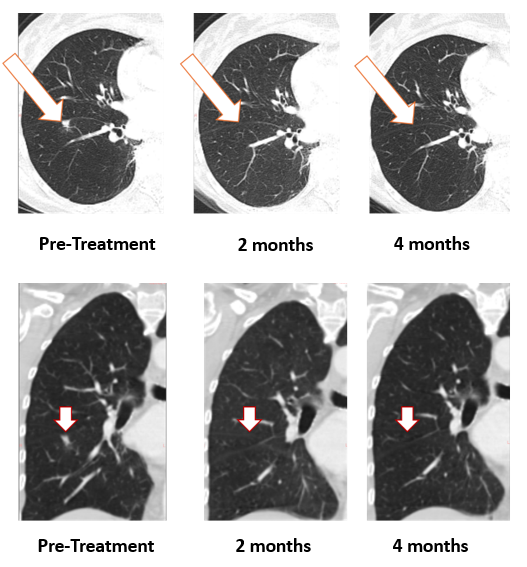

Figure 1: Treatment with Bria-OTS monotherapy resulted in 100% resolution of tumor in the lung of the metastatic breast cancer (MBC) patient following 2 months of therapy and confirmed at 4 months of therapy [1] (axial and coronal views)

As shown, the lesion in the patient’s right lung is undetectable after two months and confirmed resolved at 4 months. The updated images supersede those previously reported.

[1]Note that the other white dots in the lungs are blood vessels